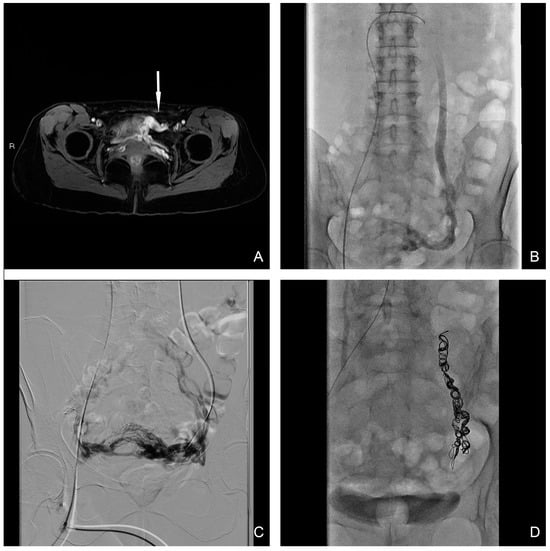

2. Materials and Methods